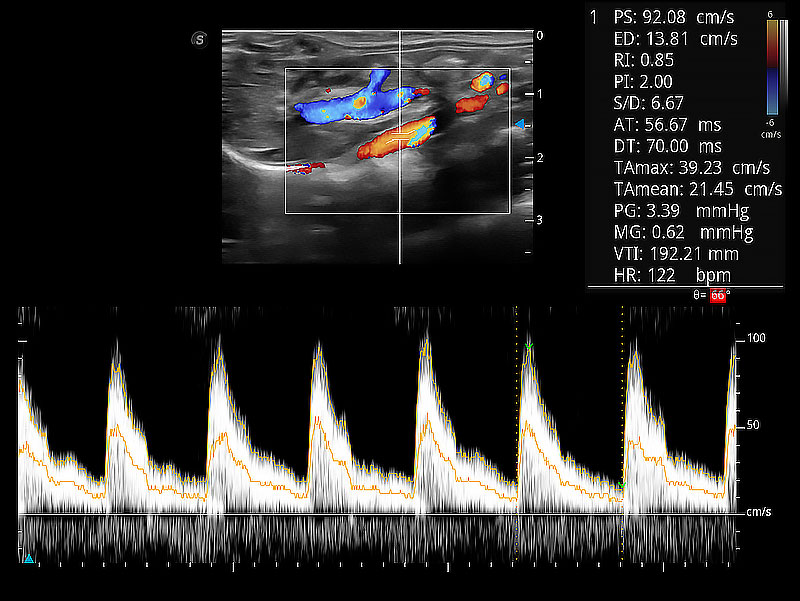

極大提升超低速微細(xì)血流的檢出能力,同時更精準(zhǔn)地濾除軟組織和超聲信號,為獸用醫(yī)生提供以往無法通過常規(guī)血流獲得的疾病診斷信息。

隨著取樣門位置改變,頻譜多普勒包絡(luò)可進(jìn)行自動眼蹤測量,且可自由配置測量的參數(shù)。